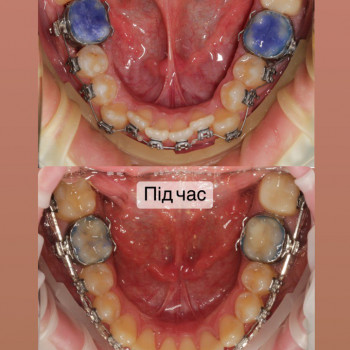

Якщо ти хочеш рівні зуби та красиву посмішку - тобі саме до нас!

Ми зробимо це на високому рівні!

А як саме наважитись на постановку брекетів?

Перший крок - це консультація ортодонта, Ви зможете дізнатись відповіді на запитання які Вас хвилюють. Перед постановкою брекетів усі зубки мають бути здорові, якщо ми бачимо карієс, його потрібно полікувати. Також потрібно зробити рентгенівські знимки для діагностики. За цей час, коли ми готуємо зуби до постановки брекетів, Ви зможете налаштуватись морально, звикнути з думкою що Ваша посмішка засяє новими барвами. На сьогоднішній час носіння брекетів являється престижним!